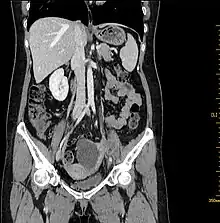

Computed tomography

Computed tomography (CT) scans is a diagnostic x-ray procedure that generates detailed cross-sectional images of the body, facilitating the detection of potential ovarian cancer spread to other organs.[16] While CT scans may not effectively visualize small ovarian tumors, they have the capability to detect larger tumors and evaluate their potential invasion into nearby structures. Additionally, CT scans can identify enlarged lymph nodes, signs of cancer spreading to the liver or other organs, and indications of an ovarian tumor impacting the kidneys or bladder. Although CT scans are not commonly used for biopsying ovarian tumors, they can be utilized in the biopsy of suspected metastases through a technique known as CT-guided needle biopsy.[16]